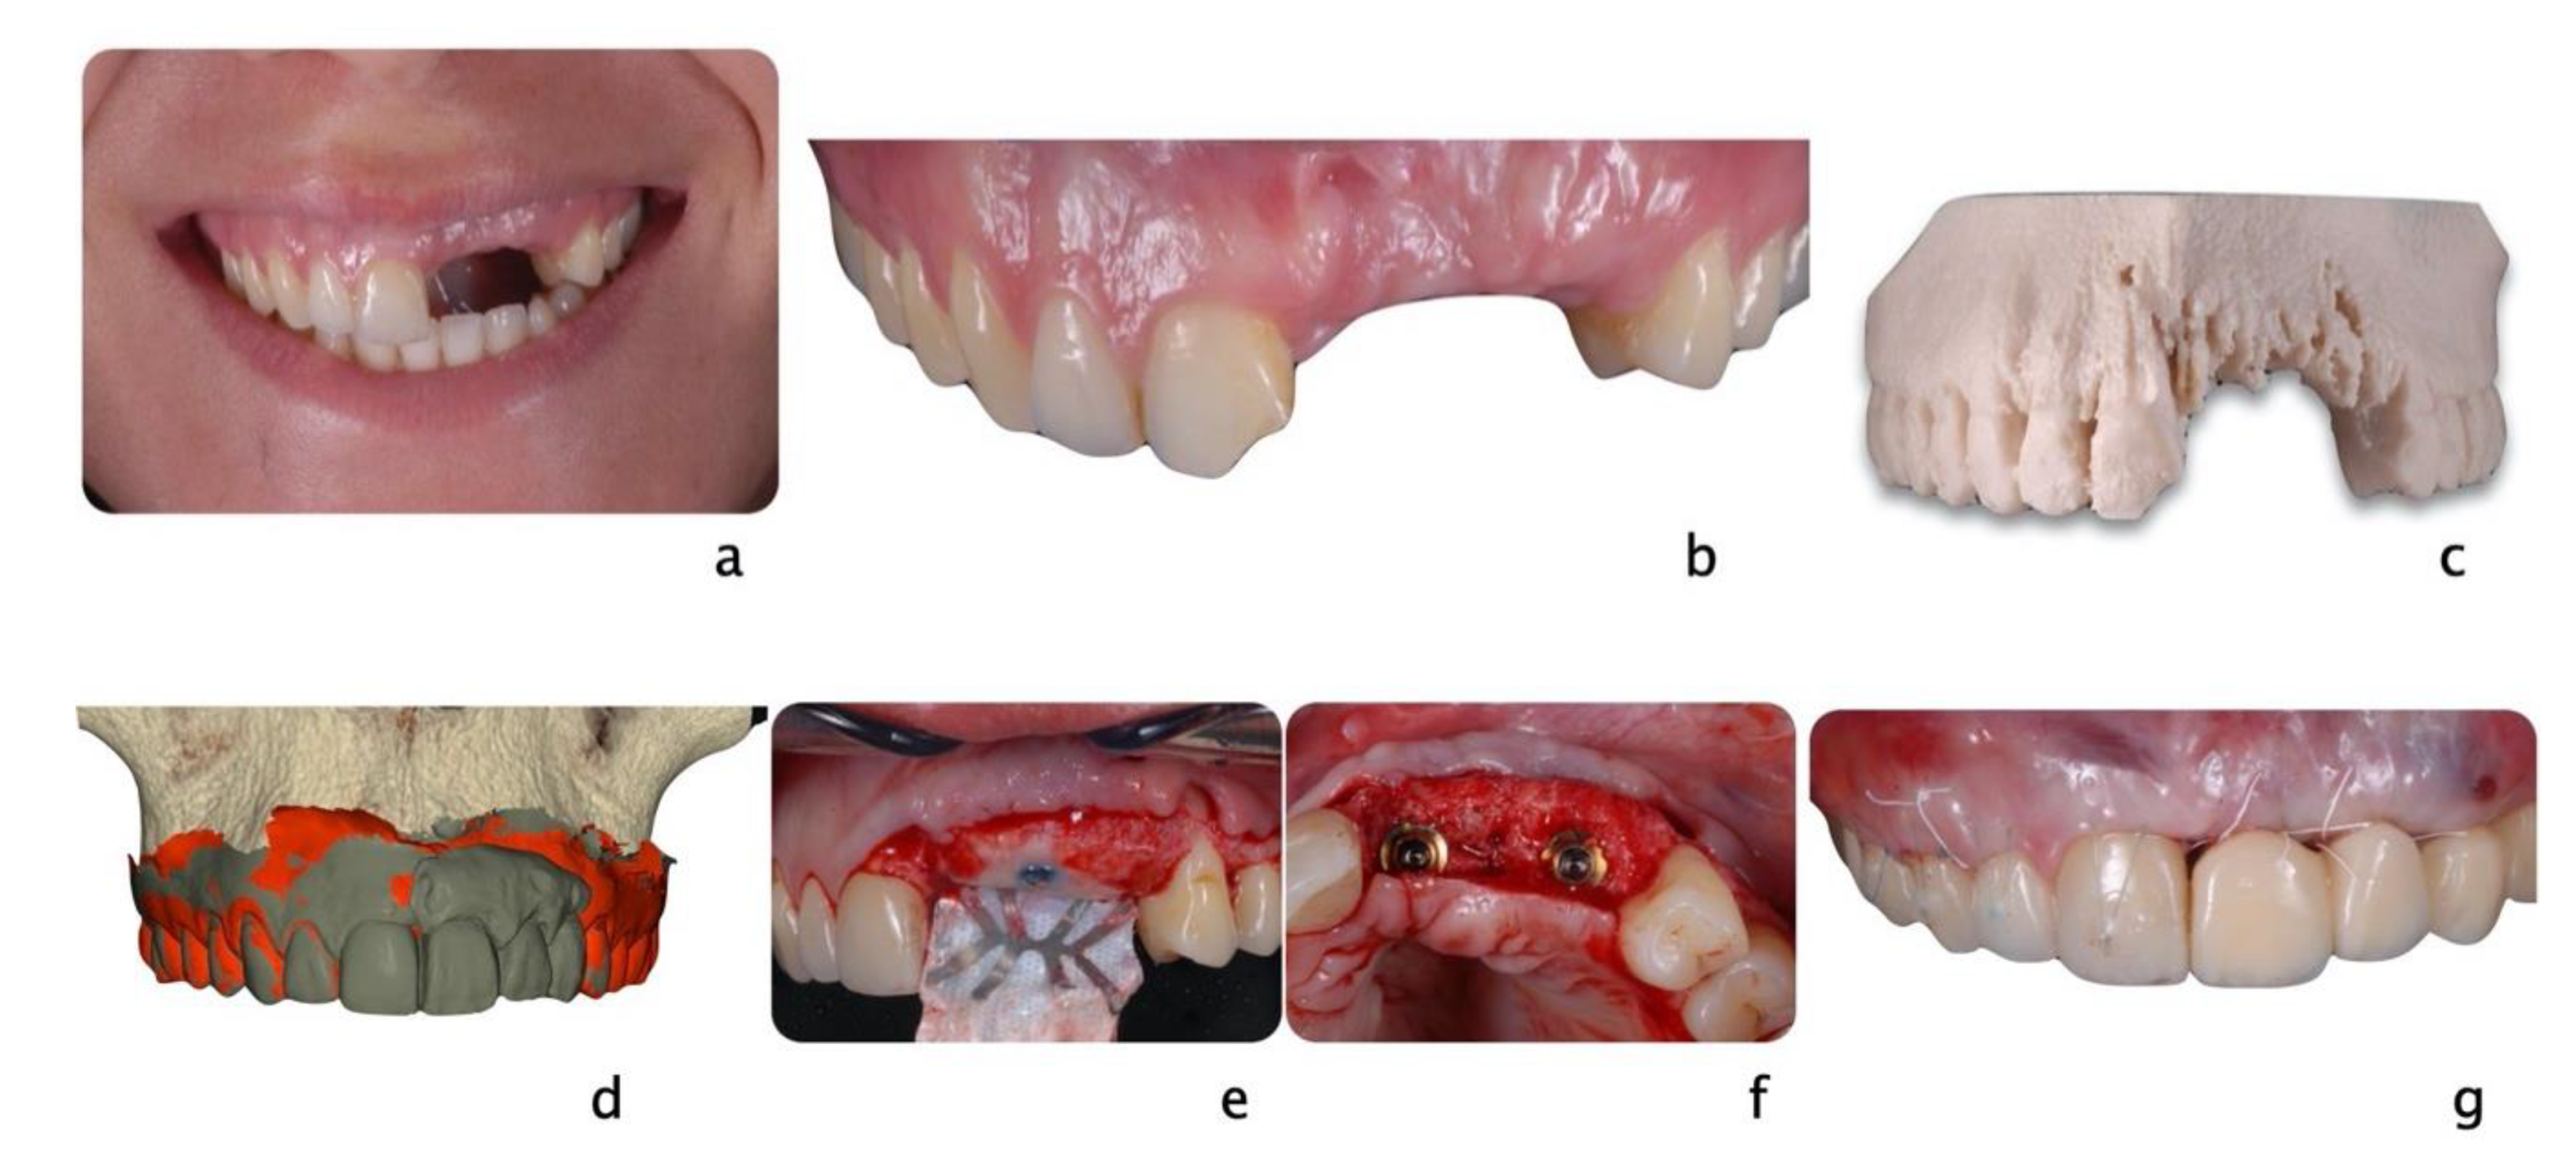

Figure 3.

A 20-year-old Asian male had #8 diagnosed with a root fractured due to sport related trauma (a). The tooth was endodontically treated, followed by healing with interposition of connective tissue (b). After healing was completed, a second sport injury involved the same tooth. The tooth mobility increased, and a periodontal lesion was diagnosed by elevated probing depth. The tooth was stabilized with orthodontic wire and patient was referred to periodontist for evaluation. Combined with malocclusion and anterior open-bite, the treatment plan was made as full-month orthodontics and auto-transplantation of #28. Tooth #8 and 28 were extracted (c,d) and a premolar replica was printed (d). After socket adjustment with the replica (e), tooth #28 was stabilized in place with sutures (f). After periodontal stabilization and verification of periodontal healing (g), the final restoration was delivered (h).